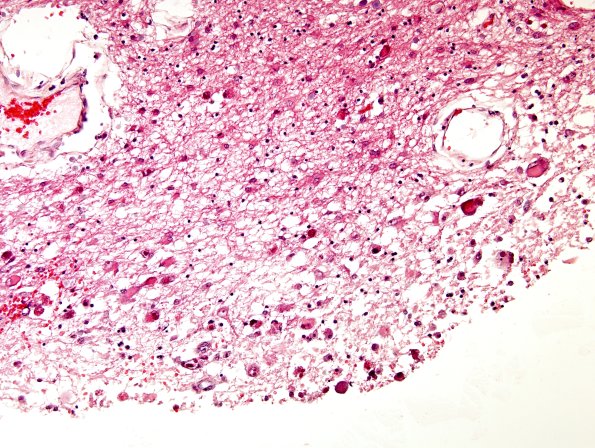

2B1,2 Sections of the cerebral hemispheres, cerebellum, brainstem and spinal cord show widespread CMV encephalitis without significant inflammation. There is also diffuse CMV ependymitis and subependymal destruction of brain tissue in the regions of the left and right lateral and the 3rd and 4th ventricles. The ependyma, shown here in the lateral ventricle, are extensively involved. (H&E)